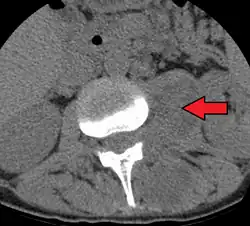

Paraspinal abscess in the psoas muscle

Psoas abscess is a collection of pus (abscess) in the iliopsoas muscle compartment.[1][2][3] It can be classified into primary psoas abscess (caused by hematogenous or lymphatic spread of a pathogen) and secondary psoas abscess (resulting from contiguous spread from an adjacent infectious focus).[3]